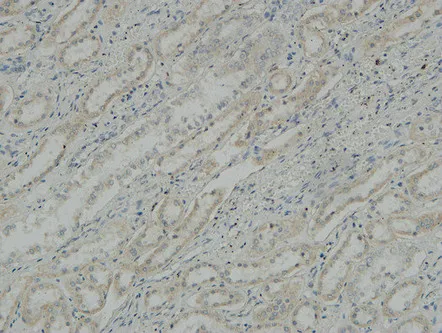

Na+/K+-ATPase α1 Rabbit Polyclonal Antibody

Cat: APRab14378

Size1:50μl Price1:$118

Size2:100μl Price2:$220

Size3:500μl Price3:$980

Size2:100μl Price2:$220

Size3:500μl Price3:$980